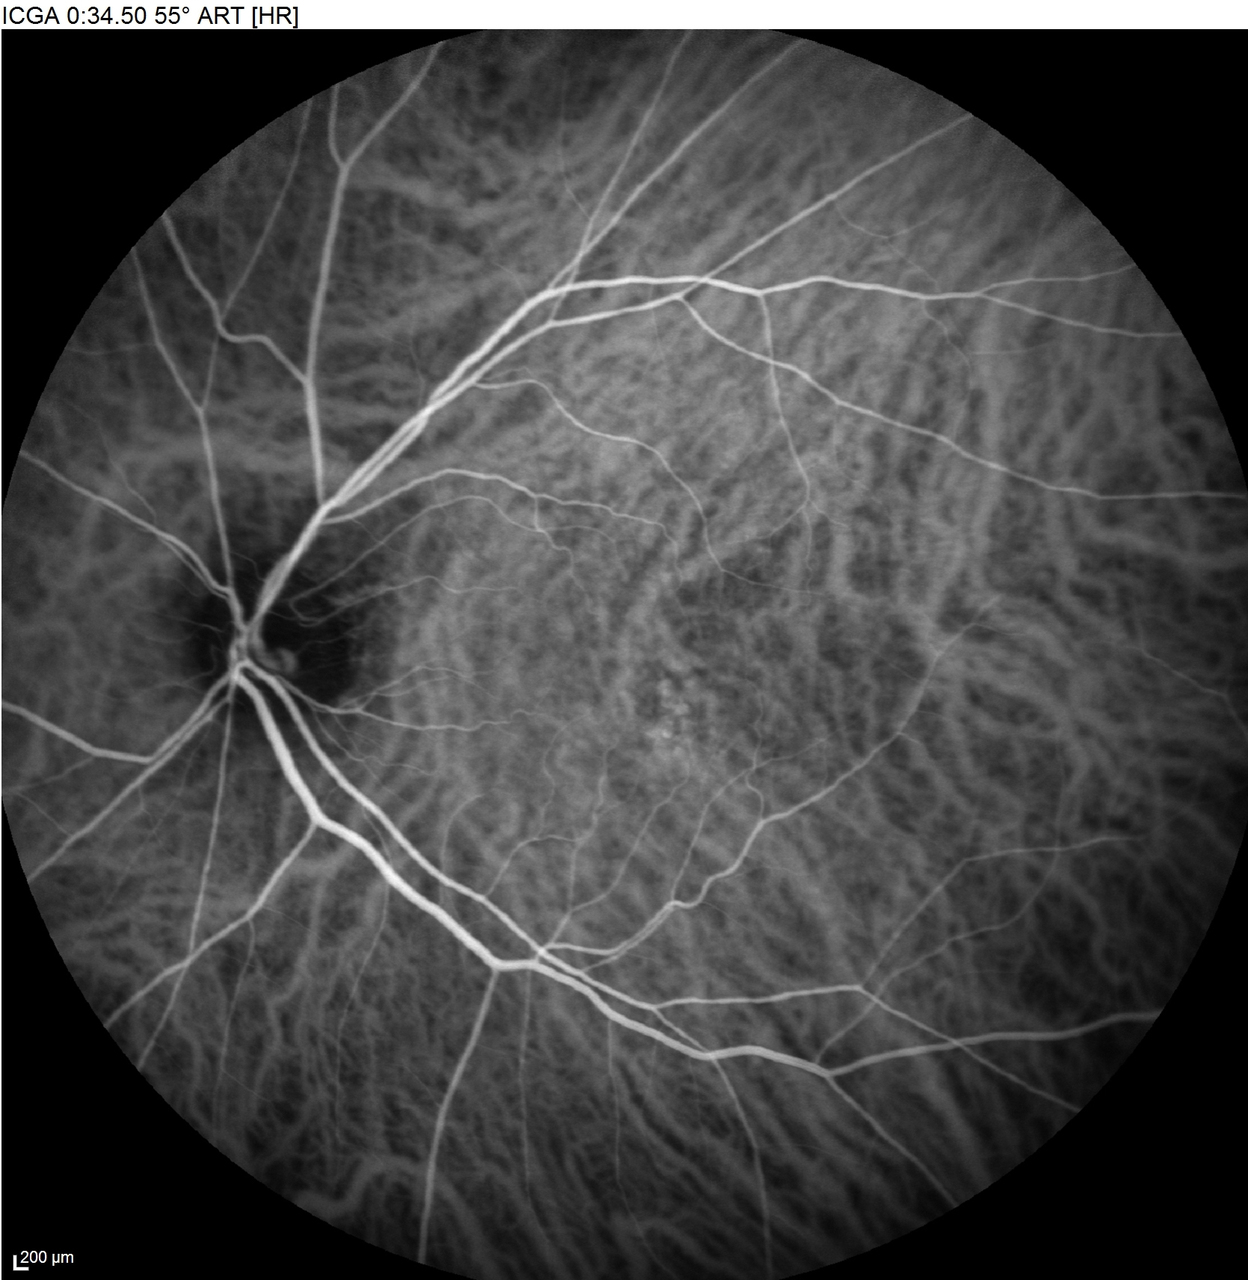

Voici les clichés de l’angiographie rétinienne à la fluorescéine et au vert d’indocyanine (ICG) :

Gauche :

Nouvelle question difficile dans ce dossier de DMLA, l’interprétation d’une angiographie rétinienne. Vous devez être stratégique et rester simple. A ce stade du dossier vous savez que vous êtes face à une DMLA exsudative, et que les néo vaisseaux de la DMLA sont d’origine choroïdienne. Vous devez donc retrouver une anomalie vasculaire à DROITE au moins en ICG, mais vu que ça saigne dans la rétine à l’OCT, cela signifie qu’on va également retrouver des anomalies en fluorescéine. Sur les 3 premiers clichés, on remarque cette lésion vasculaire rétrofovéolaire (flèche bleue) qui s’imprègne de colorant et qui n’a rien à faire ici (Si vous connaissez par cœur votre collège des enseignant d’Ophtalmologie, vous savez donc que la fovéa est une région anatomique AVASCULAIRE). Donc cette lésion en ICG, qui diffuse également très nettement en fluorescéine est totalement anormale et représente le néovaisseau choroïdien qui a réussi à soulever l’épithélium pigmentaire ET à le transpercer pour saigner directement dans la rétine. Avec de l’entrainement vous serez plus à l’aise avec cette notion.